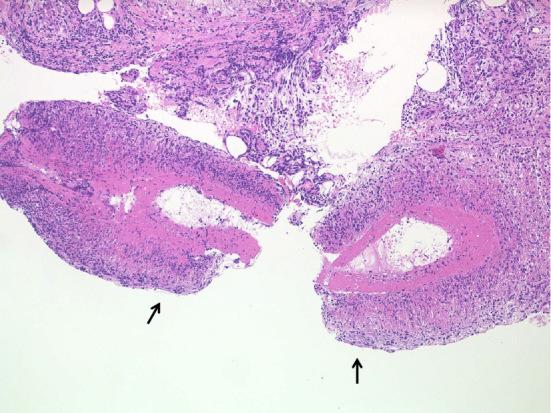

Chronic recurrent multifocal osteomyelitis (CRMO) is an autoinflammatory bone disorder that generally occurs in children and predominantly affects the long bones with marginal sclerosis. We herein report two cases of adult-onset CRMO involving the tibial diaphysis bilaterally, accompanied by polyarthritis. Magnetic resonance imaging (MRI) showed both tibial osteomyelitis and high intensity of the extensive lower leg muscles. Anti-interleukin-6 therapy with tocilizumab (TCZ) effectively controlled symptoms and inflammatory markers in both patients. High intensity of the lower leg muscles detected by MRI also improved. These cases demonstrate that CRMO should be included in the differential diagnosis of adult patients with bone pain, inflammation, and high intensity of the muscles detected by MRI. TCZ may therefore be an effective therapy for muscle inflammation of CRMO.

慢性复发性多灶性骨髓炎(CRMO)是一种自身炎症性骨病,通常发生于儿童,主要累及长骨并伴有边缘性硬化。我们在此报告两例双侧胫骨骨干受累的成人型CRMO病例,伴有多关节炎。磁共振成像(MRI)显示双侧胫骨骨髓炎以及小腿广泛肌肉的高强度信号。使用托珠单抗(TCZ)进行抗白细胞介素-6治疗有效控制了两名患者的症状和炎症标志物。MRI检测到的小腿肌肉高强度信号也有所改善。这些病例表明,CRMO应纳入对有骨痛、炎症以及MRI检测到肌肉高强度信号的成年患者的鉴别诊断中。因此,TCZ可能是治疗CRMO肌肉炎症的有效疗法。